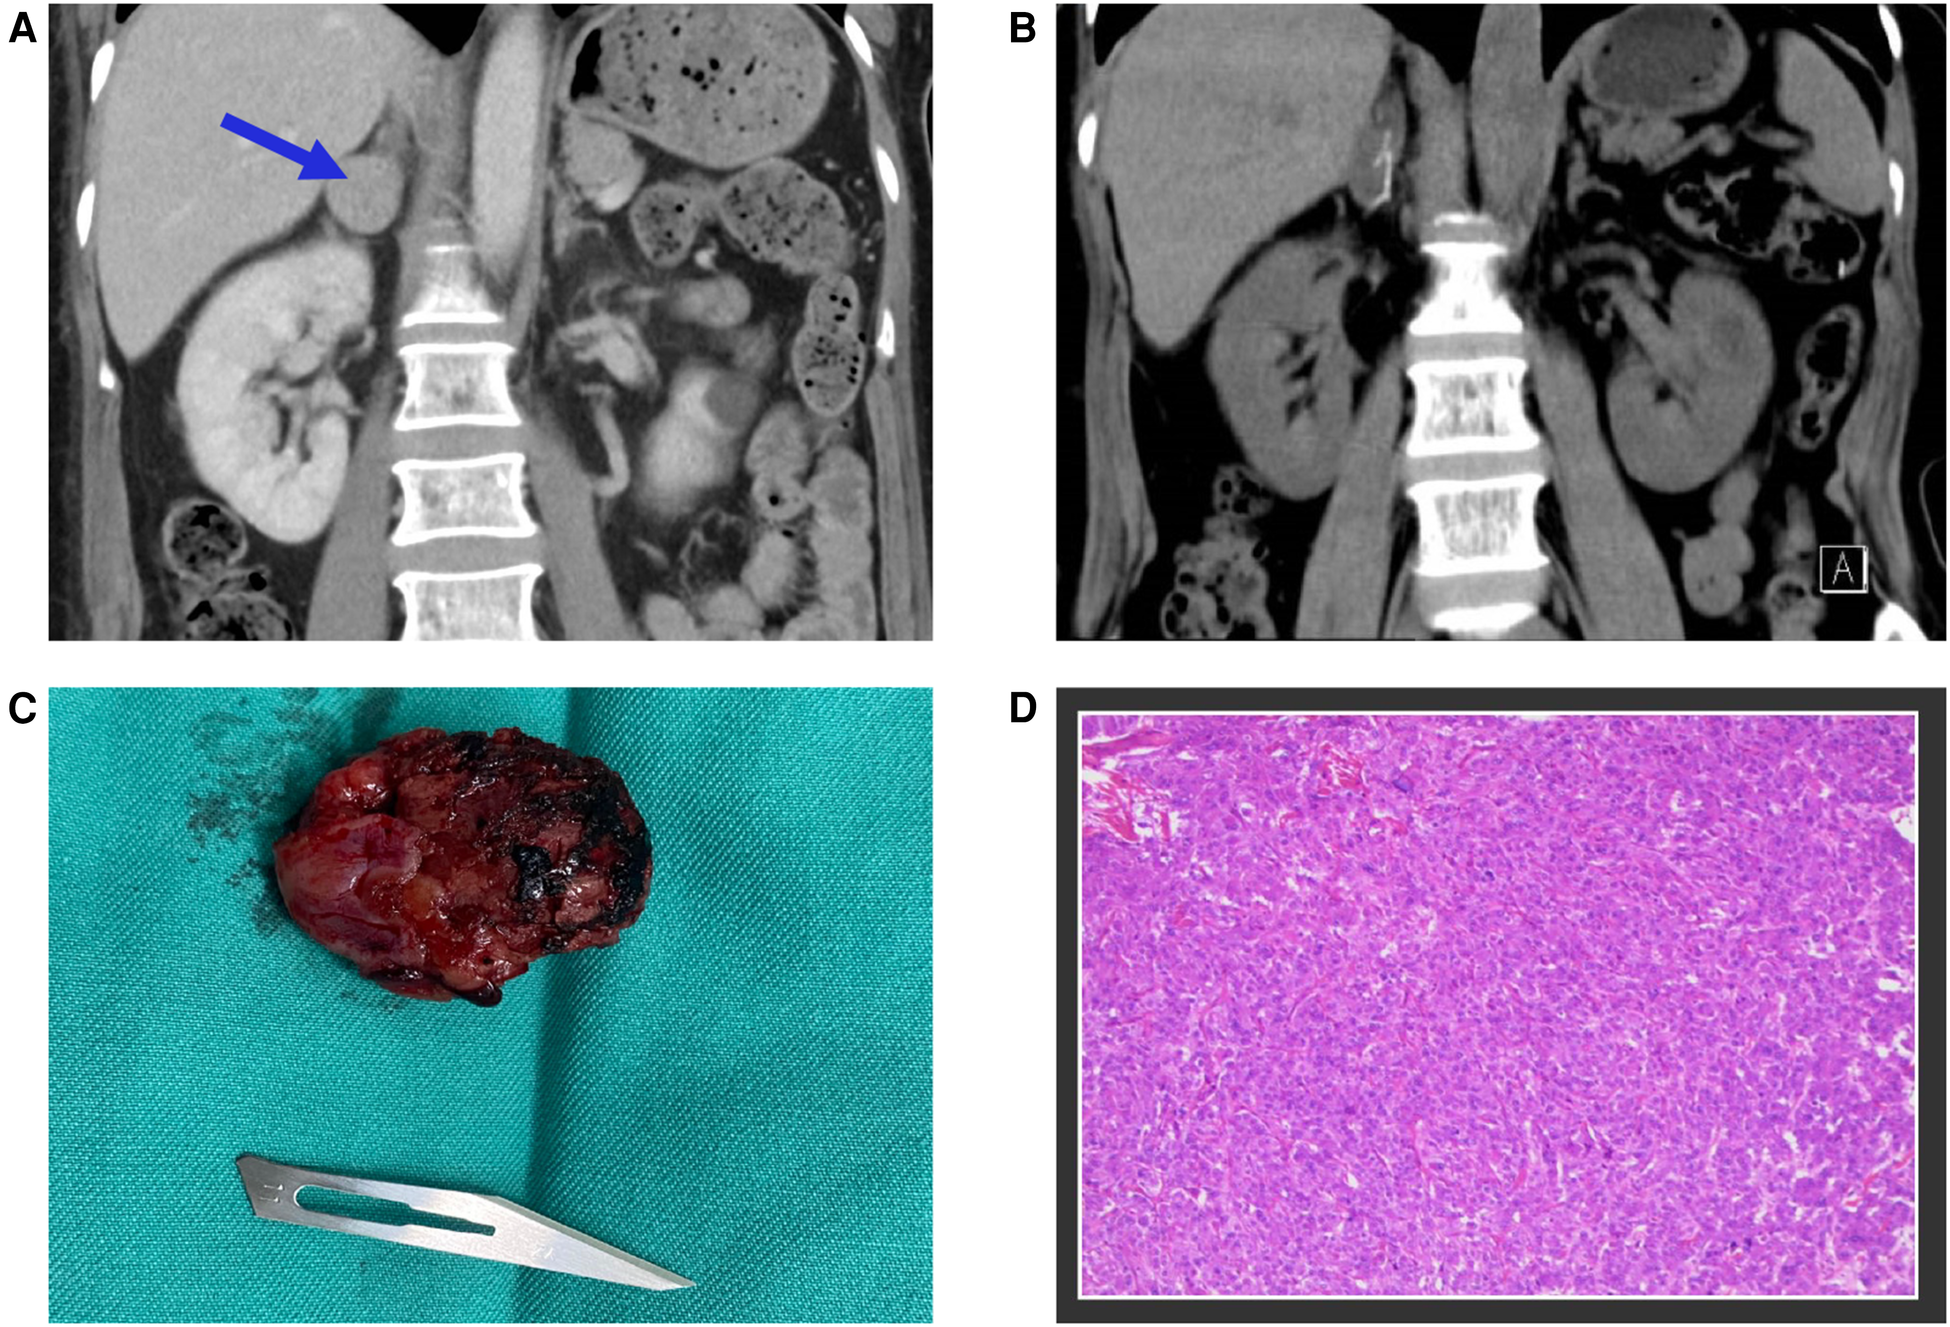

Given the fulminant myocarditis suspicion, the patient was immediately transferred to the emergency intensive care unit (EICU), and a comprehensive treatment strategy was adopted, including non-invasive ventilatory support, antiviral therapy, intravenous immunoglobulin, corticosteroids, anti-infective therapy, and aggressive heart failure management. However, the patient's condition deteriorated, with persistently elevated cardiac markers, and considerations for mechanical circulatory support emerged. On the third day of hospitalization, a sudden and significant increase in blood pressure discouraged the usage of extra-corporeal membrane oxygenation (ECMO) and prompted a reassessment of the initial diagnosis. It is worth noting that despite the administration of medications such as Sodium Nitroprusside and Calcium channel blockers, the patient's blood pressure remained challenging to control. At this point, a contrast-enhanced abdominal CT scan revealed a 26 × 26 × 25 mm mass in the right adrenal gland, leading to suspicion of pheochromocytoma (Figure 3A). This suspicion was supported by elevated plasma metanephrine (2.15 nmol/L; normal < 0.50 nmol/L), plasma normetanephrine (1.24 nmol/L; normal < 0.90 nmol/L), urinary metanephrine (1,954 nmol/24 h; normal < 216 nmol/24 h), and urinary normetanephrine (1,399 nmol/24 h; normal < 312 nmol/24 h). Upon further questioning, the patient stated that she had been having episodic headaches with vomiting and sweating, as well as elevated blood pressure, usually post-Domperidone administration. In light of these findings, the diagnosis was revised from fulminant myocarditis to pheochromocytoma-induced cardiomyopathy, also known as a pheochromocytoma crisis.

Figure 3

(A) The contrast-enhanced abdominal CT scan identified a 26 × 26 × 25 mm mass located in the right adrenal gland, marked with blue arrows. (B) The postoperative follow-up CT scan revealed the complete excision of the tumor mass. (C) A photograph of the surgically removed tumor during the operation. (D) Microscopic examination of the adrenal gland tumor confirmed the diagnosis of pheochromocytoma.

Following the initiation of alpha-blockade therapy, the patient's condition gradually improved, with the normalization of various clinical and biochemical markers, improvement in left ventricular ejection fraction (50.8%), and resolution of ECG (Figure 1B) and radiological findings (Figure 2B). Four weeks following alpha-blockade therapy, the patient underwent successful laparoscopic right adrenalectomy (Figures 3B,C), with the pathology report confirming adrenal pheochromocytoma (Figure 3D).